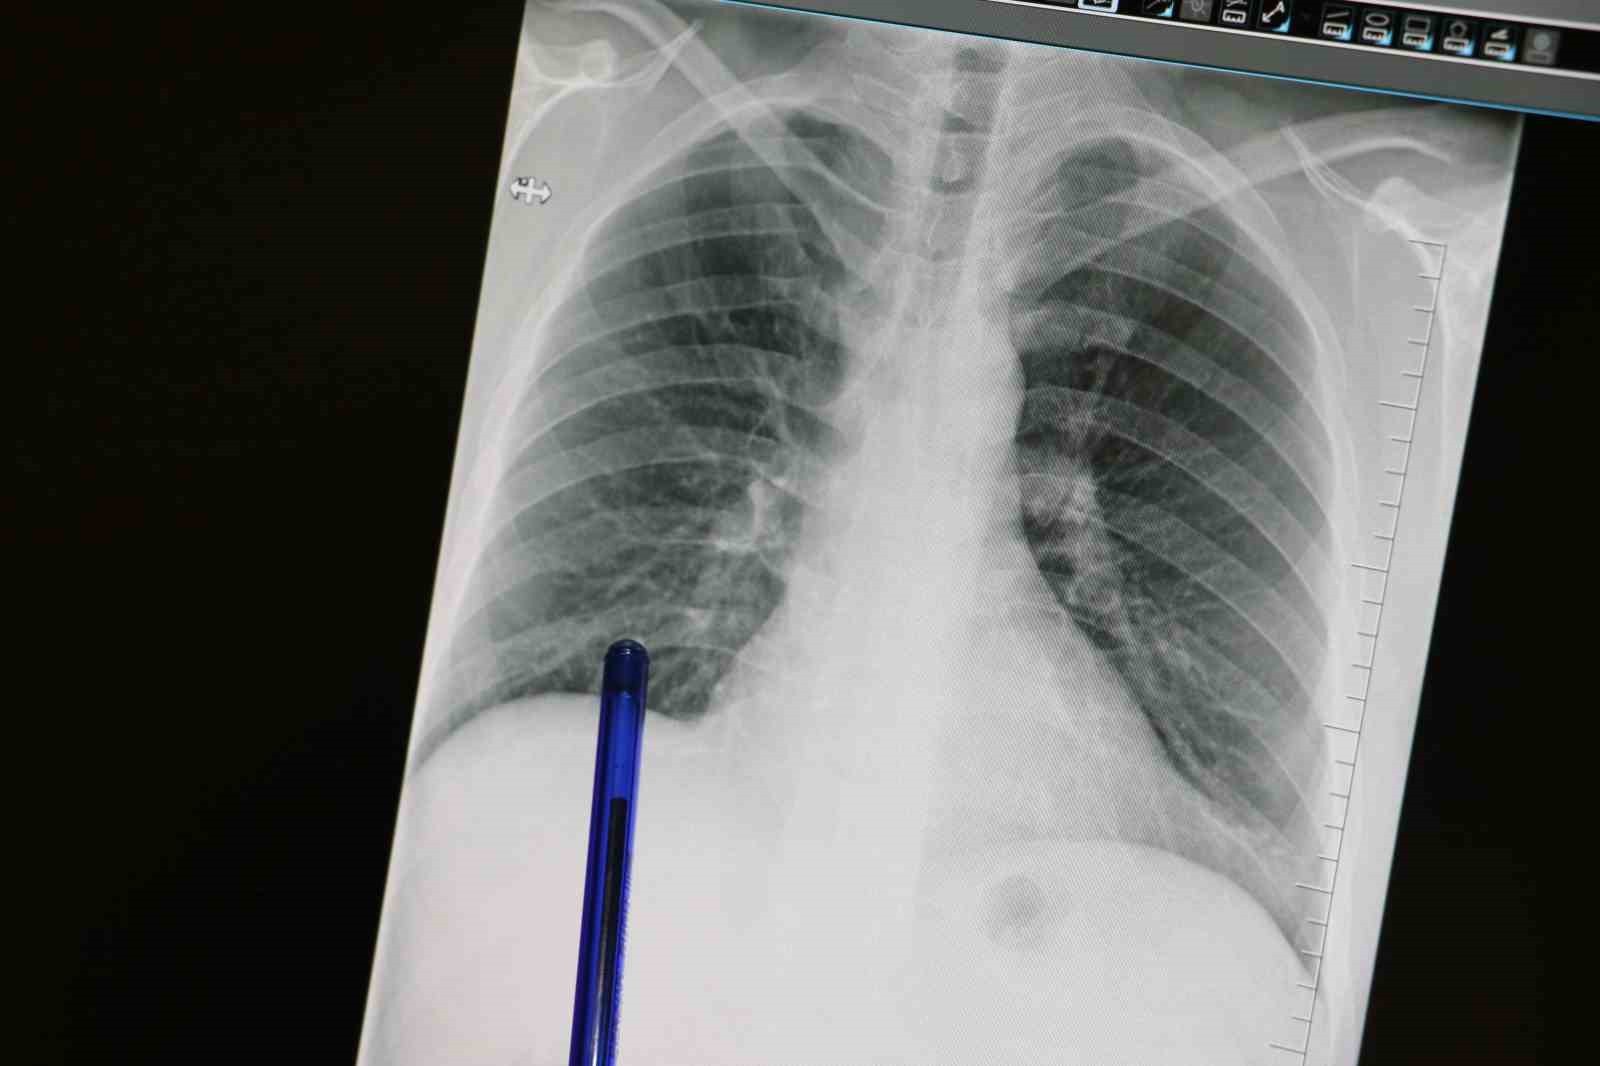

Basit Semptomlar Akciğer Kanserinin Habercisi Olabilir

Medicana Sivas Hastanesi Göğüs Hastalıkları Uzmanı Dr. Büşra Yayla Yerlikaya, öksürük ve balgam çıkarma gibi sıradan görünen belirtilerin akciğer kanserinin habercisi olabileceğine dikkat çekti. Dr. Yerlikaya, erken tanının akciğer kanserinde tedavi başarısını belirgin şekilde artırdığını belirtti.

Akciğer kanseri ve erken tanının önemi

Kasım ayı, Türkiye'de Akciğer Kanseri Farkındalık Ayı olarak kabul ediliyor. Akciğer kanseri, akciğer dokusundaki hücrelerin kontrolsüz çoğalmasıyla oluşan ve diğer organlara yayılabilen ciddi bir hastalık olarak tanımlanıyor. Hastalık genellikle erken evrede belirti vermediği için geç fark edilebilmekte ve bu durum tedavi şansını azaltmaktadır.

Akciğer kanserinin sık görülen belirtileri arasında uzun süren öksürük, balgamda kan, nefes darlığı, kilo kaybı ve göğüs ağrısı yer alıyor. Özellikle sigara içen bir kişide yeni başlayan veya karakteri değişen öksürük varsa bir göğüs hastalıkları uzmanından değerlendirme alınması gerektiği vurgulandı. Sabahları görülen balgam ve öksürükte karakter değişikliği veya artışın önemli bir uyarı işareti olabileceği belirtildi.

Dr. Yerlikaya, 50 yaş üzeri ve özellikle 20 paket yıl ve daha fazla sigara öyküsü olan kişilerin düşük doz tomografi ile taranmasının, hastalığın erken yakalanmasını sağlayarak tedavi şansını ciddi şekilde artıracağını söyledi. Ayrıca sigarayı bırakmanın her yaşta faydalı olduğunu; bırakıldıktan sonraki yıllarda akciğer kanseri riskinin belirgin biçimde azaldığını hatırlattı.